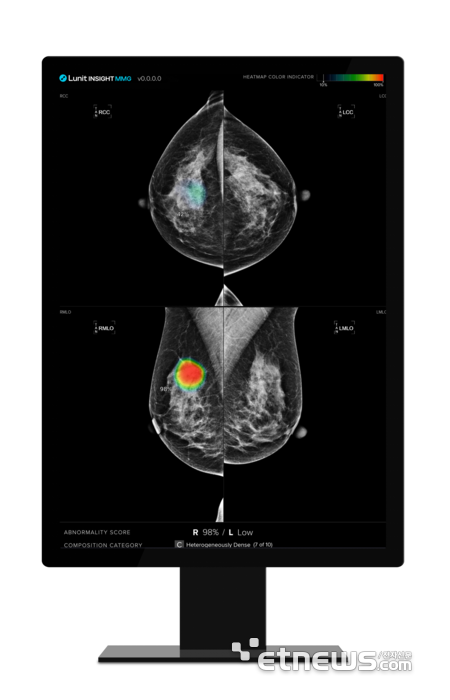

AI 리서치·캔서스크리닝 부문 역시 데이터 거버넌스를 강화하는 개편을 단행했다. 전반적인 데이터 획득, 관리를 책임지는 데이터 인텔리전스팀 외에 브레스트, 체스트팀을 별도 신설했다. 각각 유방암과 흉부 엑스레이 특화 데이터 마이닝을 맡는다. 이를 통해 유방암 진단 인공지능(AI) 솔루션 '루닛 인사이트 MMG'와 흉부 엑스레이 AI 분석 솔루션 '루닛 인사이트 CXR' 등 주요 솔루션 경쟁력을 높이겠다는 취지다.

이번 R&D 조직개편은 주력 제품 사업화가 완성되면서 성장 가속화를 위한 조직 혁신이 배경이다. 루닛은 현재 △응급질환 판별 AI 솔루션 '루닛 인사이트 CXR 트리아지' △유방암 진단 AI 솔루션 '루닛 인사이트 MMG' △3차원 유방단층촬영술 AI 분석 솔루션 '루닛 인사이트 DBT' 3종의 미국 식품의약국(FDA) 허가를 획득, 글로벌 사업을 활발히 펼치고 있다. 올해엔 생성형AI 기술을 적용한 흉부 엑스레이 판독문 자동생성기까지 FDA 허가를 노리고 있다.